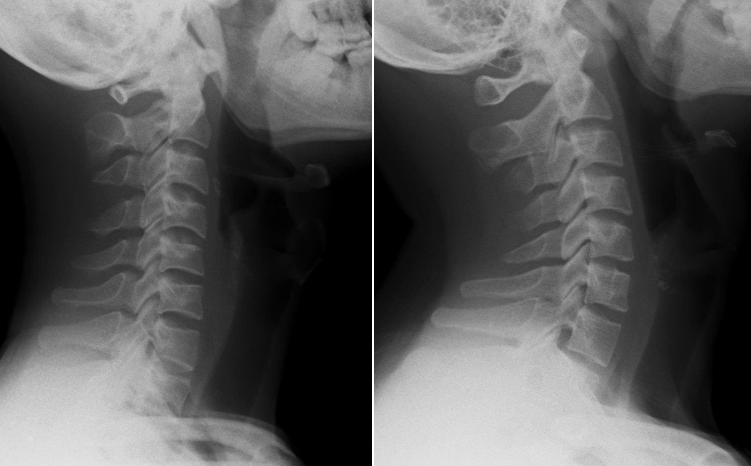

Kết quả chụp X-quang cho thấy cột sống cổ của bệnh nhân mất độ cong sinh lý, khiến các đốt sống cổ gần như xếp dọc thay vì có độ ưỡn ra trước như bình thường.

Cột sống cổ của nam thanh niên thẳng đứng (ảnh 1) và cột sống cổ bình thường (ảnh 2). (Ảnh: BSCC)

Tiến sĩ, bác sĩ Ngô Thị Kim Oanh - Phó Trưởng khoa Châm cứu - Dưỡng sinh, Bệnh viện Đại học Y Dược TP.HCM - Cơ sở 3 cho biết, ở người trưởng thành khỏe mạnh, cột sống cổ có độ cong nhẹ về phía trước - gọi là độ ưỡn sinh lý giúp phân bổ đều lực từ đầu xuống vai và thân trên, hấp thu lực chấn động từ các hoạt động thường ngày (đi, đứng, chạy...), giảm tải trọng lên đĩa đệm và khớp liên đốt sống

Khi đường cong này bị mất, cột sống trở nên “thẳng như cây gậy” làm tăng áp lực lên các đĩa đệm, khớp, dây chằng và cơ quanh cổ. Về lâu dài, điều đó có thể dẫn đến thoái hóa sớm, thoát vị đĩa đệm cổ, chèn ép rễ thần kinh hoặc tủy sống, gây ra các triệu chứng như đau, tê tay, chóng mặt, thậm chí yếu cơ.